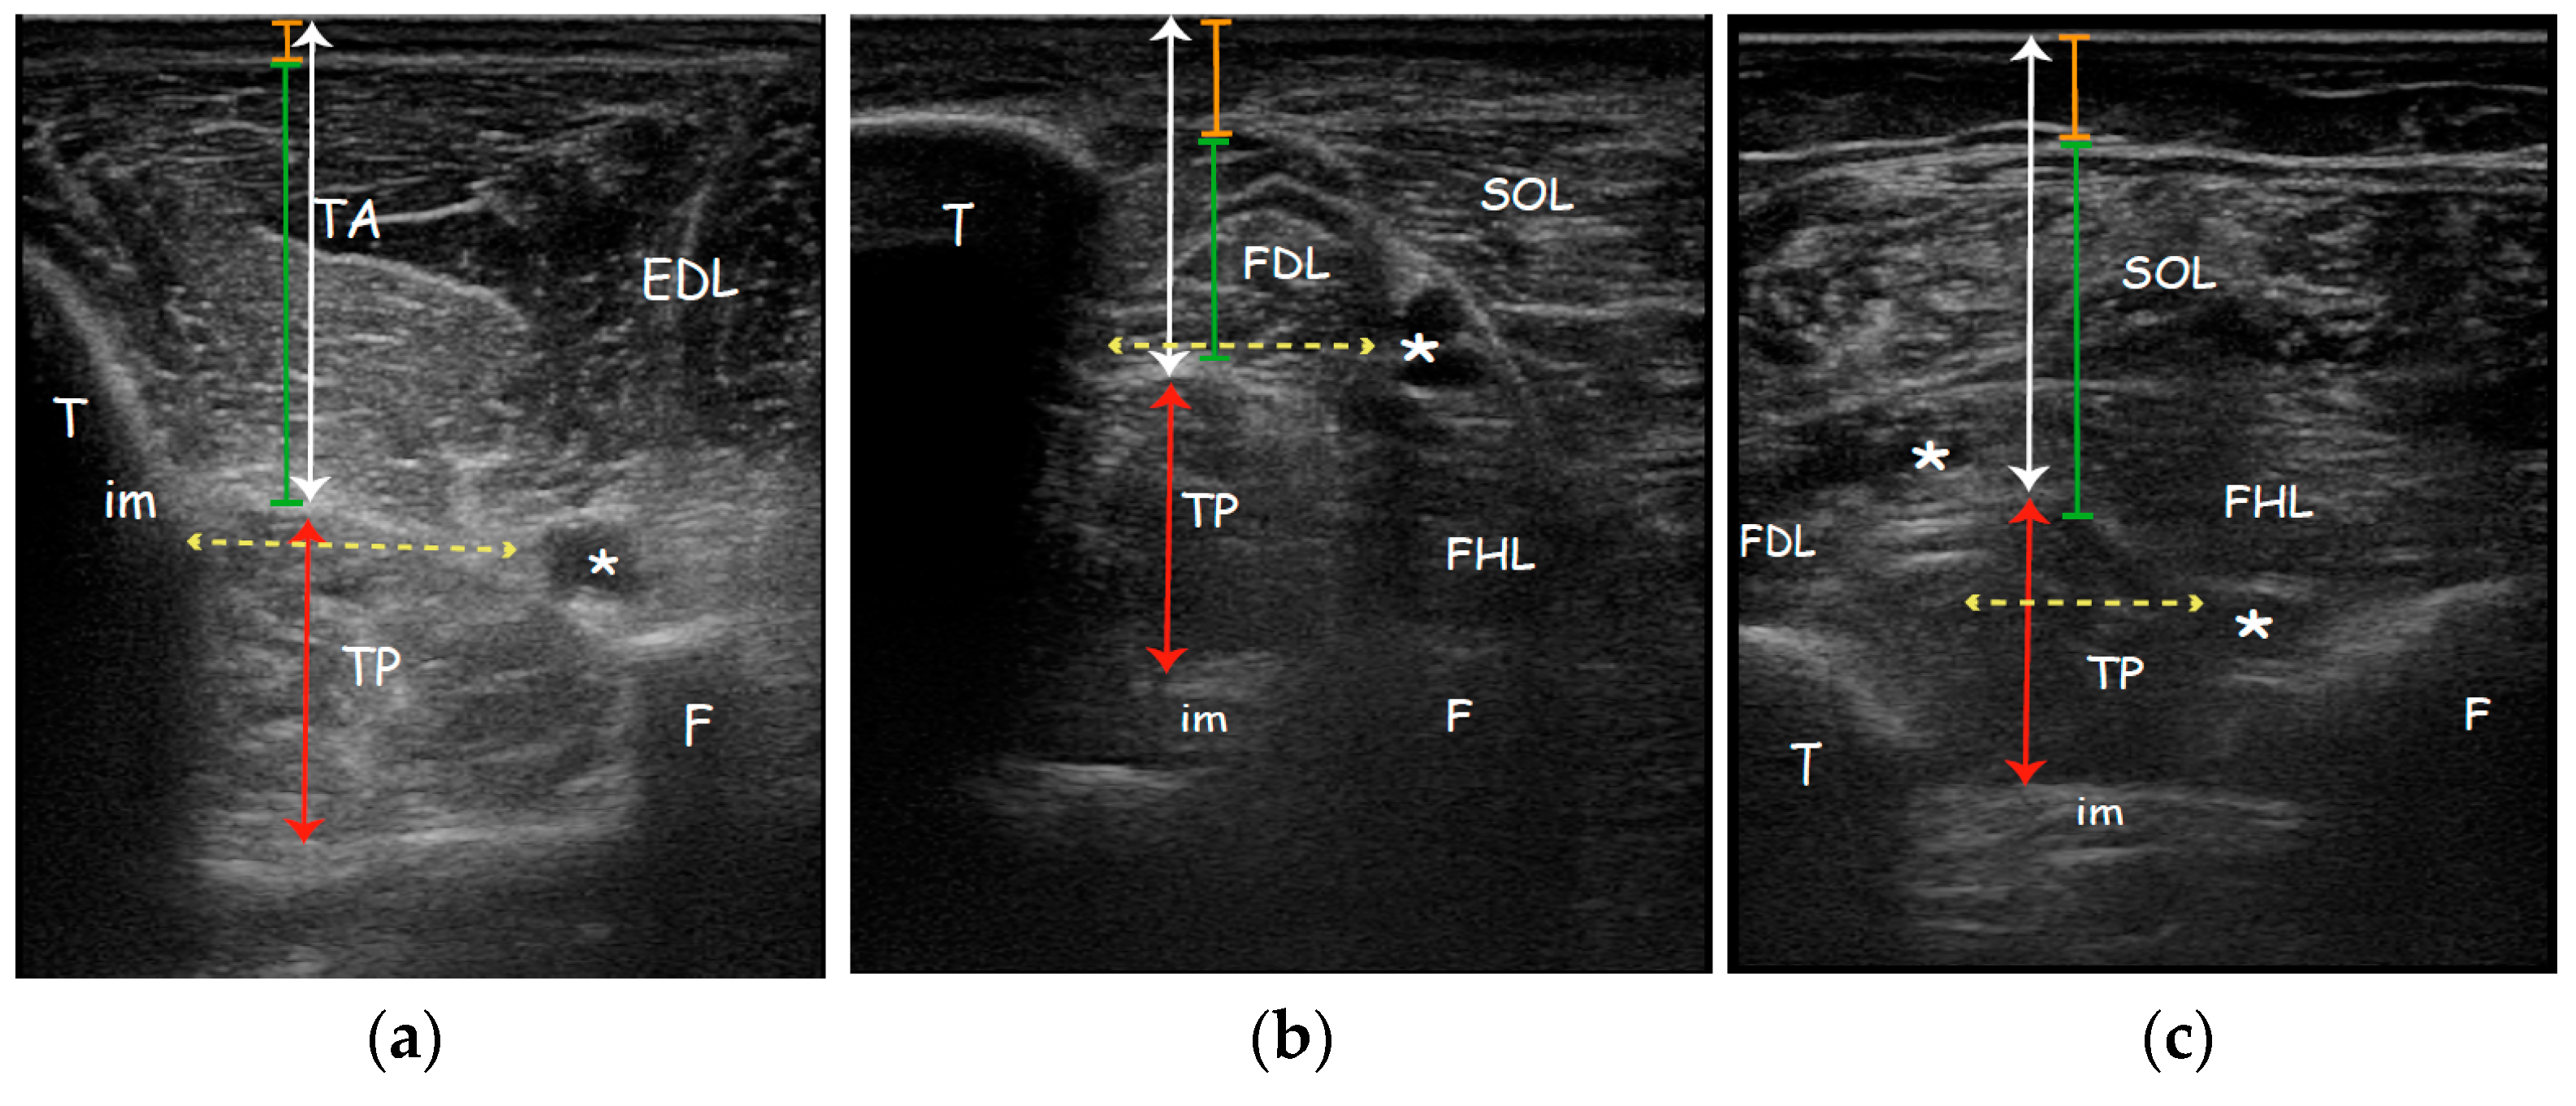

During the anterior approach (Figure 1a), the TP is reached at the upper third of the leg after passing the tibialis anterior and the interosseous membrane which appears as a hyperechoic band between the tibia and the fibula; passing the membrane could lead to more pain to the patient. Moreover, attention must be paid to the anterior neurovascular bundle (anterior tibial artery and vein and deep peroneal nerve) running close to the posterolateral border of the tibia. Although it is indeed easy to place the probe and to access the TP by this view, we usually do not perform this technique due to lack of visibility of the whole belly muscle behind the tibia, the prerequisite to use a needle more than 30 mm long, the need to perforate the interosseous membrane and the resultant increased pain for the patient. Moreover, a recent study characterizing the microscopic structure and sensory nerve endings of the interosseus membrane had found that interosseous membrane may play a role in proprioception [32]. Therefore, it is better to preserve such structure from being perforated by the needle and save any possible mechanoreceptors as possible.

Figure 1.

Right to left: Probe position to evaluate tibialis posterior on the axial plane; Anatomical scheme of axial section of the leg correlated with US scan; representative US axial real scan, healthy subject. (a) Anterior approach; (b) Posteromedial approach; (c) Posterior approach. Abbreviations: TA tibialis anterior muscle; EDL extensor digitorum longus muscle; TP tibialis posterior muscle; SOL soleus muscle; FDL flexor digitorum longus muscle; FHL flexor hallucis longus muscle; T tibia; F fibula; im interosseous membrane; * neurovascular bundle.

During the posteromedial approach (Figure 1b), the patient lies supine with the leg extra rotated; the probe is placed in the distal third of the leg and the needle should be passed through a thin layer of soleus and flexor digitorum longus muscle (FDL) between the posterolateral border of the tibia and the posterior tibial neurovascular bundle. The advantages of this technique are the minor depth of the muscle that can be reached using the 30 mm needle, the less overlying muscle layer and so the minor muscle tissue to pass, the major thickness of TP due to the scan over its major axis and the less risk to overpassing the belly muscle.

During the posterior approach (Figure 1c), the TP is reached after passing the soleus and the flexor hallucis longus and between the posterior neurovascular bundle (posterior tibial artery and vein and tibial nerve) medially and the peroneal artery and vein laterally. We should not advise this access for novice operators because it is more difficult to distinguish the border of the TP and to differentiate the TP from other structures; it could be asked of the patient to actively move his toes or the clinician could passively move them in order to visualize better the adjacent muscle (FHL, FLD) thus isolating the TP. Moreover, due to the depth of TP (30.64 ± 3.46 mm) it cannot be used the routine needle length of 30 mm. Finally, the prone position of the patient may be difficult to reach or could be uncomfortable for a patient with hemiparesis post-stroke.

The TP muscle was identified on the surface using EUROMUSCULUS/USPRM spasticity approach for the anterior approach (25% of the distance from the fibular head to the lateral malleolus, behind the posterior border of the tibia) [42]; for the posteromedial approach, the TP muscle was located on the posteromedial surface of the leg using the Silvestri Muda Orlandi (distal third of the leg) [43]; the posterior approach was evaluated on the posterior surface at the at the junction of the middle and lower thirds of the leg with the probe placed at the posterior side of the leg perpendicular to the virtual line extending from the middle of the popliteal fossa to the intermalleolar line [44] (Figure 1).